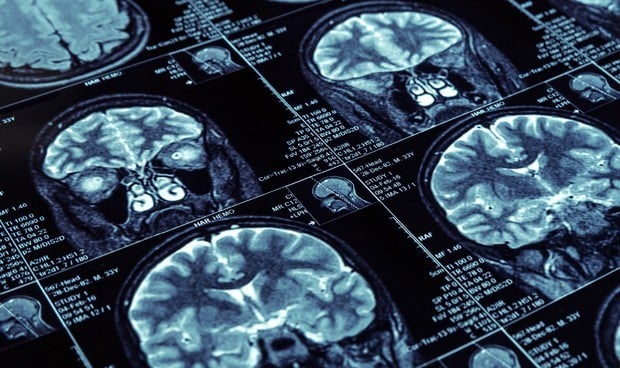

La enfermedad por Covid persistente se está identificando cada vez más debido a la permanencia de síntomas como dificultades neurocognitivas, fatiga profunda, debilidades musculares y depresión, los cuales durarían entre  3 a 12 semanas después de la infección con SARS-CoV-2, según un estudio publicado en la revista Oxford Open Immunology. Este hallazgo abre un puente en el campo de la neurología por las secuelas del virus en el sistema nervioso central (SNC).

Efectos del SARS-CoV-2 en el SNC

Varias infecciones virales pueden causar daños importantes a la estructura y función del SNC y dar lugar a la aparición de encefalitis, encefalopatías tóxicas o lesiones desmielinizantes. Esto se ha explicado anteriormente en parte por la capacidad de estos virus de "invadir" el SNC, potencialmente dañando la barrera hematoencefálica, provocando daño nervioso directo y activando microglia y astrocitos en el cerebro y conduciendo a un efecto proinflamatorio Estado a nivel central.

Se han detectado transcripciones de ARN del SARS-CoV-2 en una pequeña cantidad de tejidos cerebrales humanos a partir de estudios recientes de autopsias, lo que respalda la idea de que este virus podría afectar el SNC y el tejido cerebral.

Estudios recientes han proporcionado pruebas de la capacidad neuroinvasiva del SARS-CoV-2 e identificado características patológicas con infiltrados mínimos de células inmunitarias.